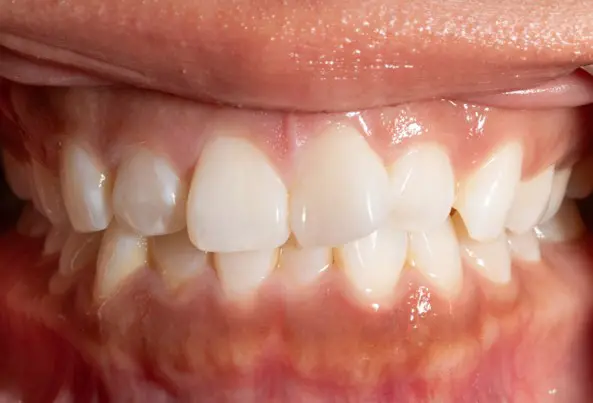

Crowding

Before

After